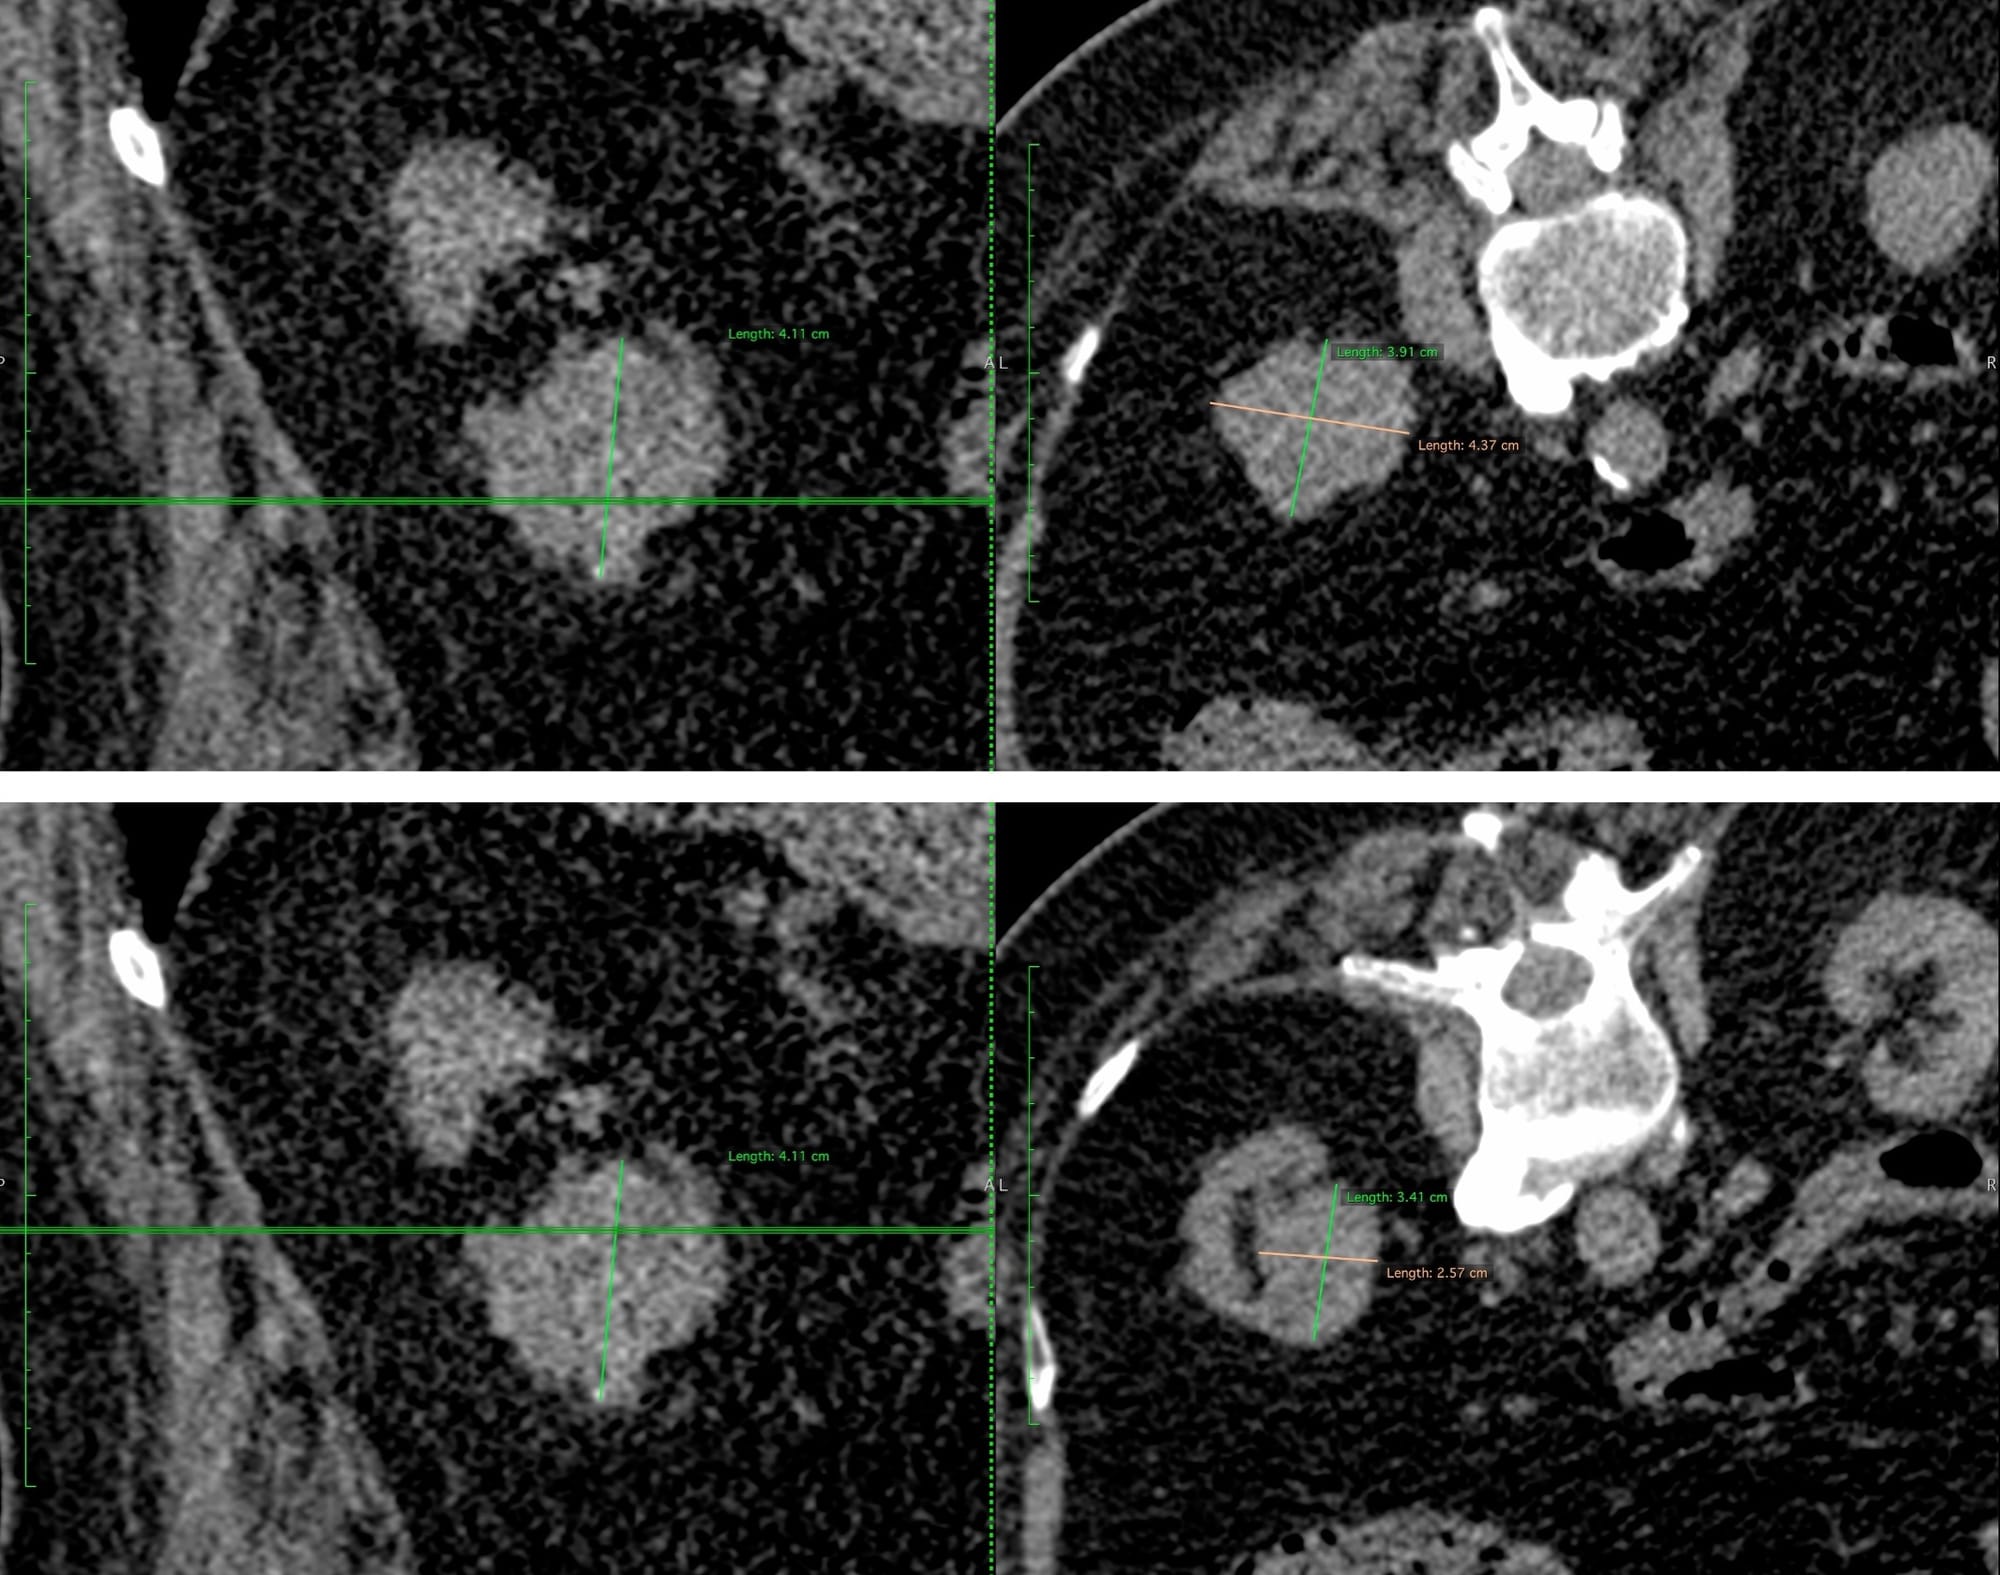

A 75-years old man with multiple comorbidities had a solid renal neoplasm > 4 cm. He and his family decided to go ahead with cryoablation after sifting through all possible options with their urologist and oncologist.

Since this is a > 4 cm lesion, two ablations had to be done, one inferiorly and one superiorly as this plan shows.